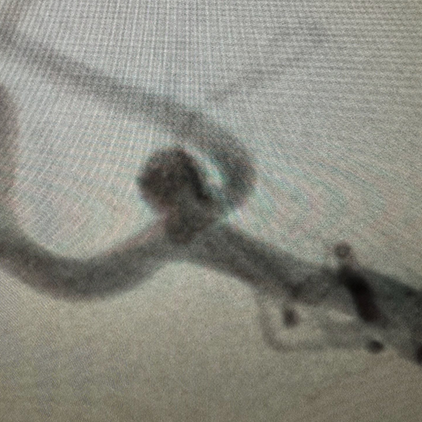

We provide devices and treatment of complex brain aneurysms and vascular malformations free of cost. These are some of the complex brain aneurysm we have recently treated in Pakistan. Devices and catheters used for all procedures were provided by Pakistan Stroke Initiative, and in some cases charges for hospitalization as well.

Although we typically don’t take photos of our patients and their families, many of those we have treated have made special requests for it. Visiting physicians from abroad have consistently been impressed by the gratitude and appreciation shown by our patients and their families for the care they receive.

All of these photos have been shared with the permission of the patients and their families.